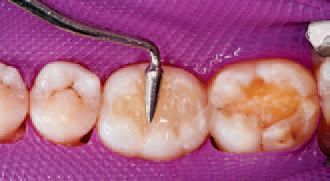

After inspecting the old amalgam restorations (Fig. 2), a rubber dam was then placed (Fig. 3). Next, using Sybron Dental’s Axis course diamond bur, KS3, the amalgam restorations and all damaged tooth structure were removed (Fig. 4).